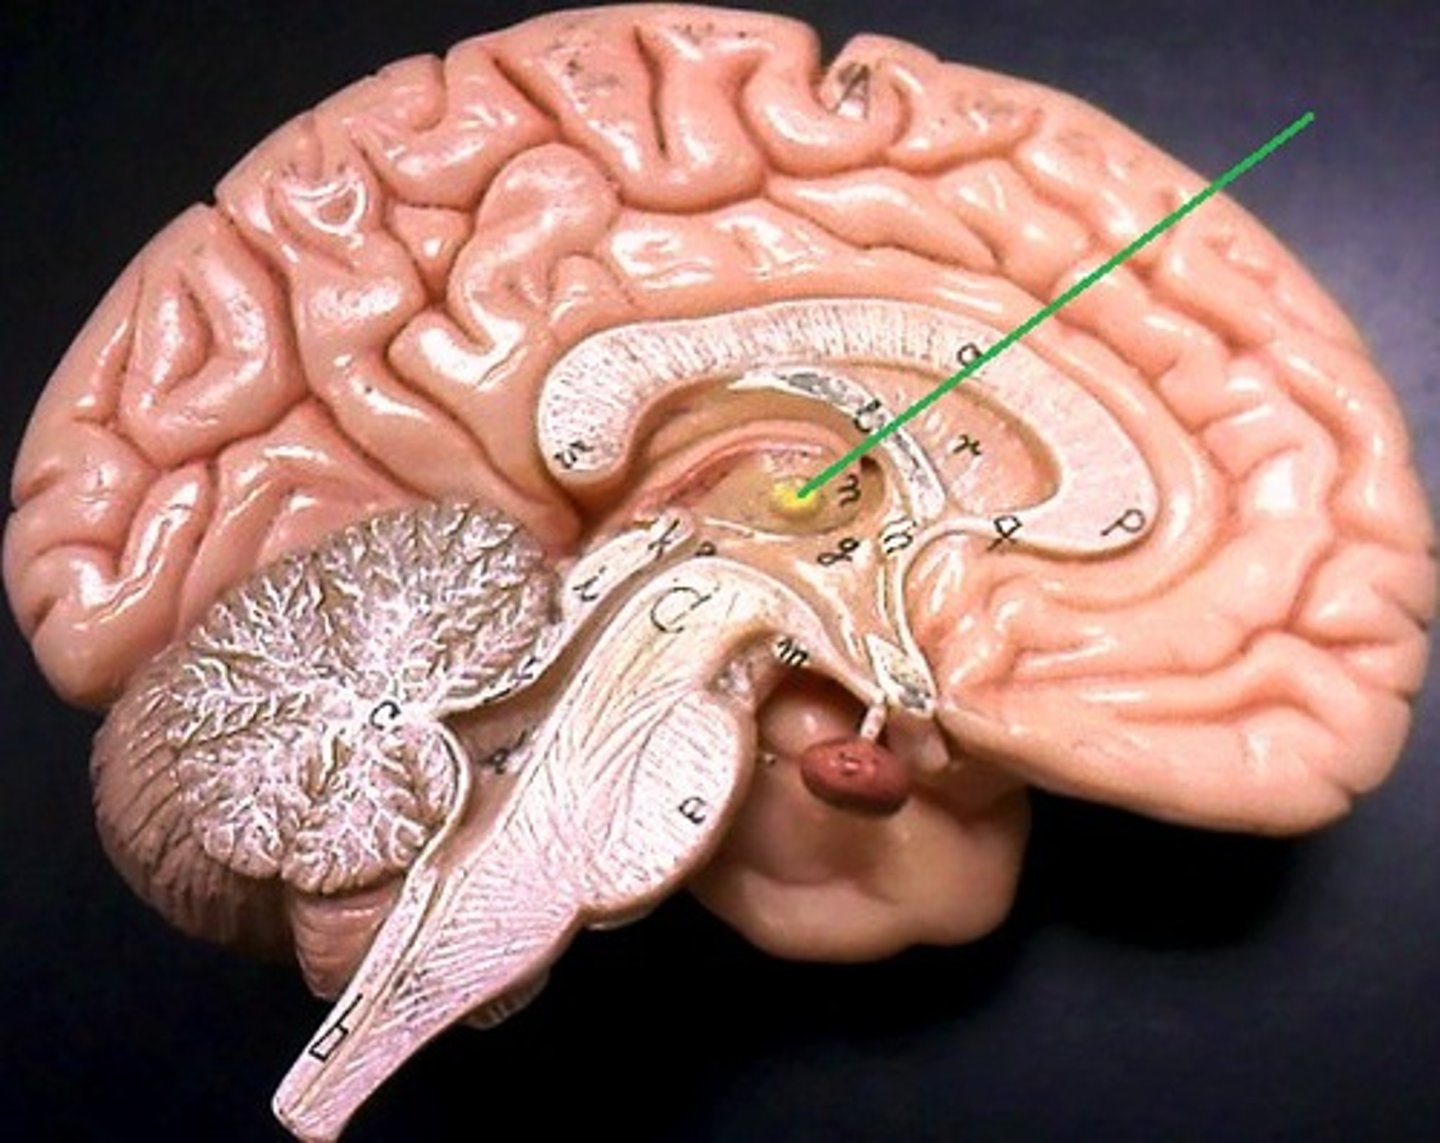

hypothalamus

thalamus

hypophysis (pituitary gland)

infundibulum

intermediate mass of thalamus

pineal gland

choroid plexus (of ventricles)

third ventricle